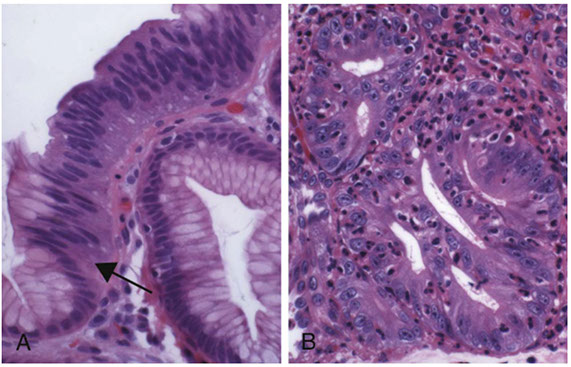

Dysplasia in Barrett esophagus. A) Abrupt transition from Barrett metaplasia to low-grade dysplasia (arrow).  B) Architectural irregularities, including gland-within-gland, or cribriform profiles in high-grade dysplasia